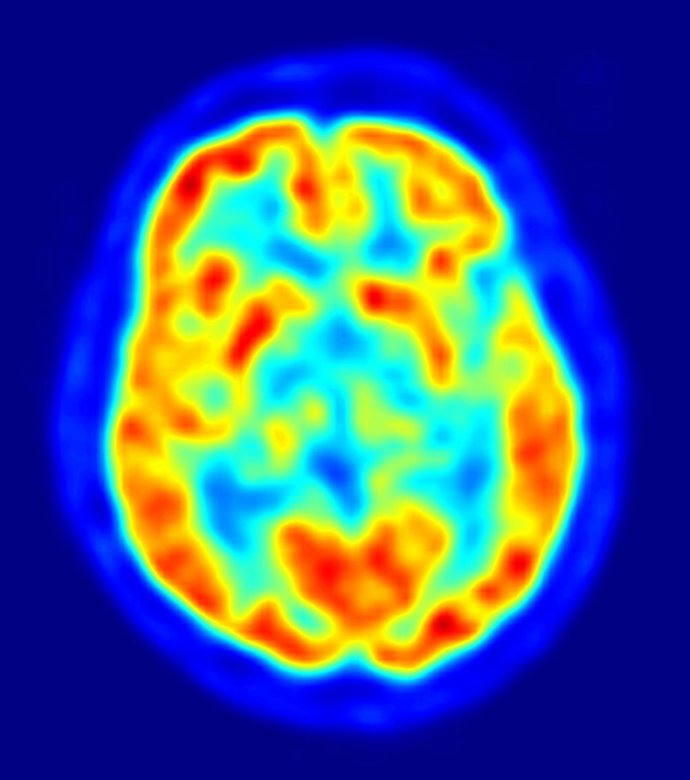

Científicos del Scripps Research Institute (Estados Unidos) han logrado usar neuronas en modelos cerebrales de ratones y controlar al menos en parte un tipo de recuerdos, un primer paso que podría llevar a comprender mejor el proceso de formación de la memoria y quizá, a debilitar los pensamientos ligados a la esquizofrenia o el trastorno de estrés postraumático. Los resultados de este estudio se publican este viernes en la revista especializada 'Science'.

Los investigadores saben desde hace décadas que estimular varias regiones cerebrales puede activar conductas e incluso recuerdos. Entender cómo se desarrollan estas funciones en el cerebro y se dan normalmente --convirtiéndonos en lo que somos-- ha sido una meta mucho más compleja de alcanzar.